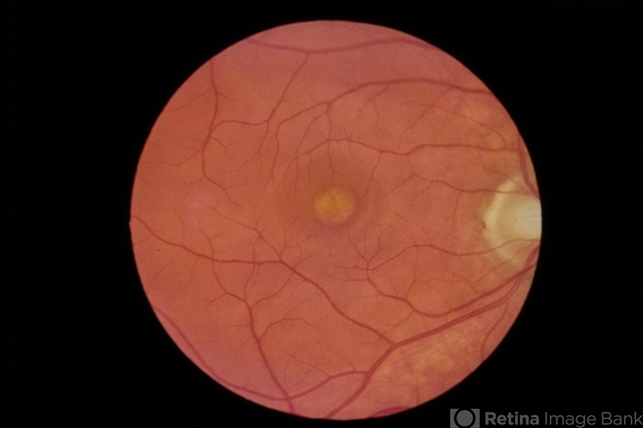

- adult vitelliform dystrophy

- Central, creamy elevation of pigment epithelium without drusen.